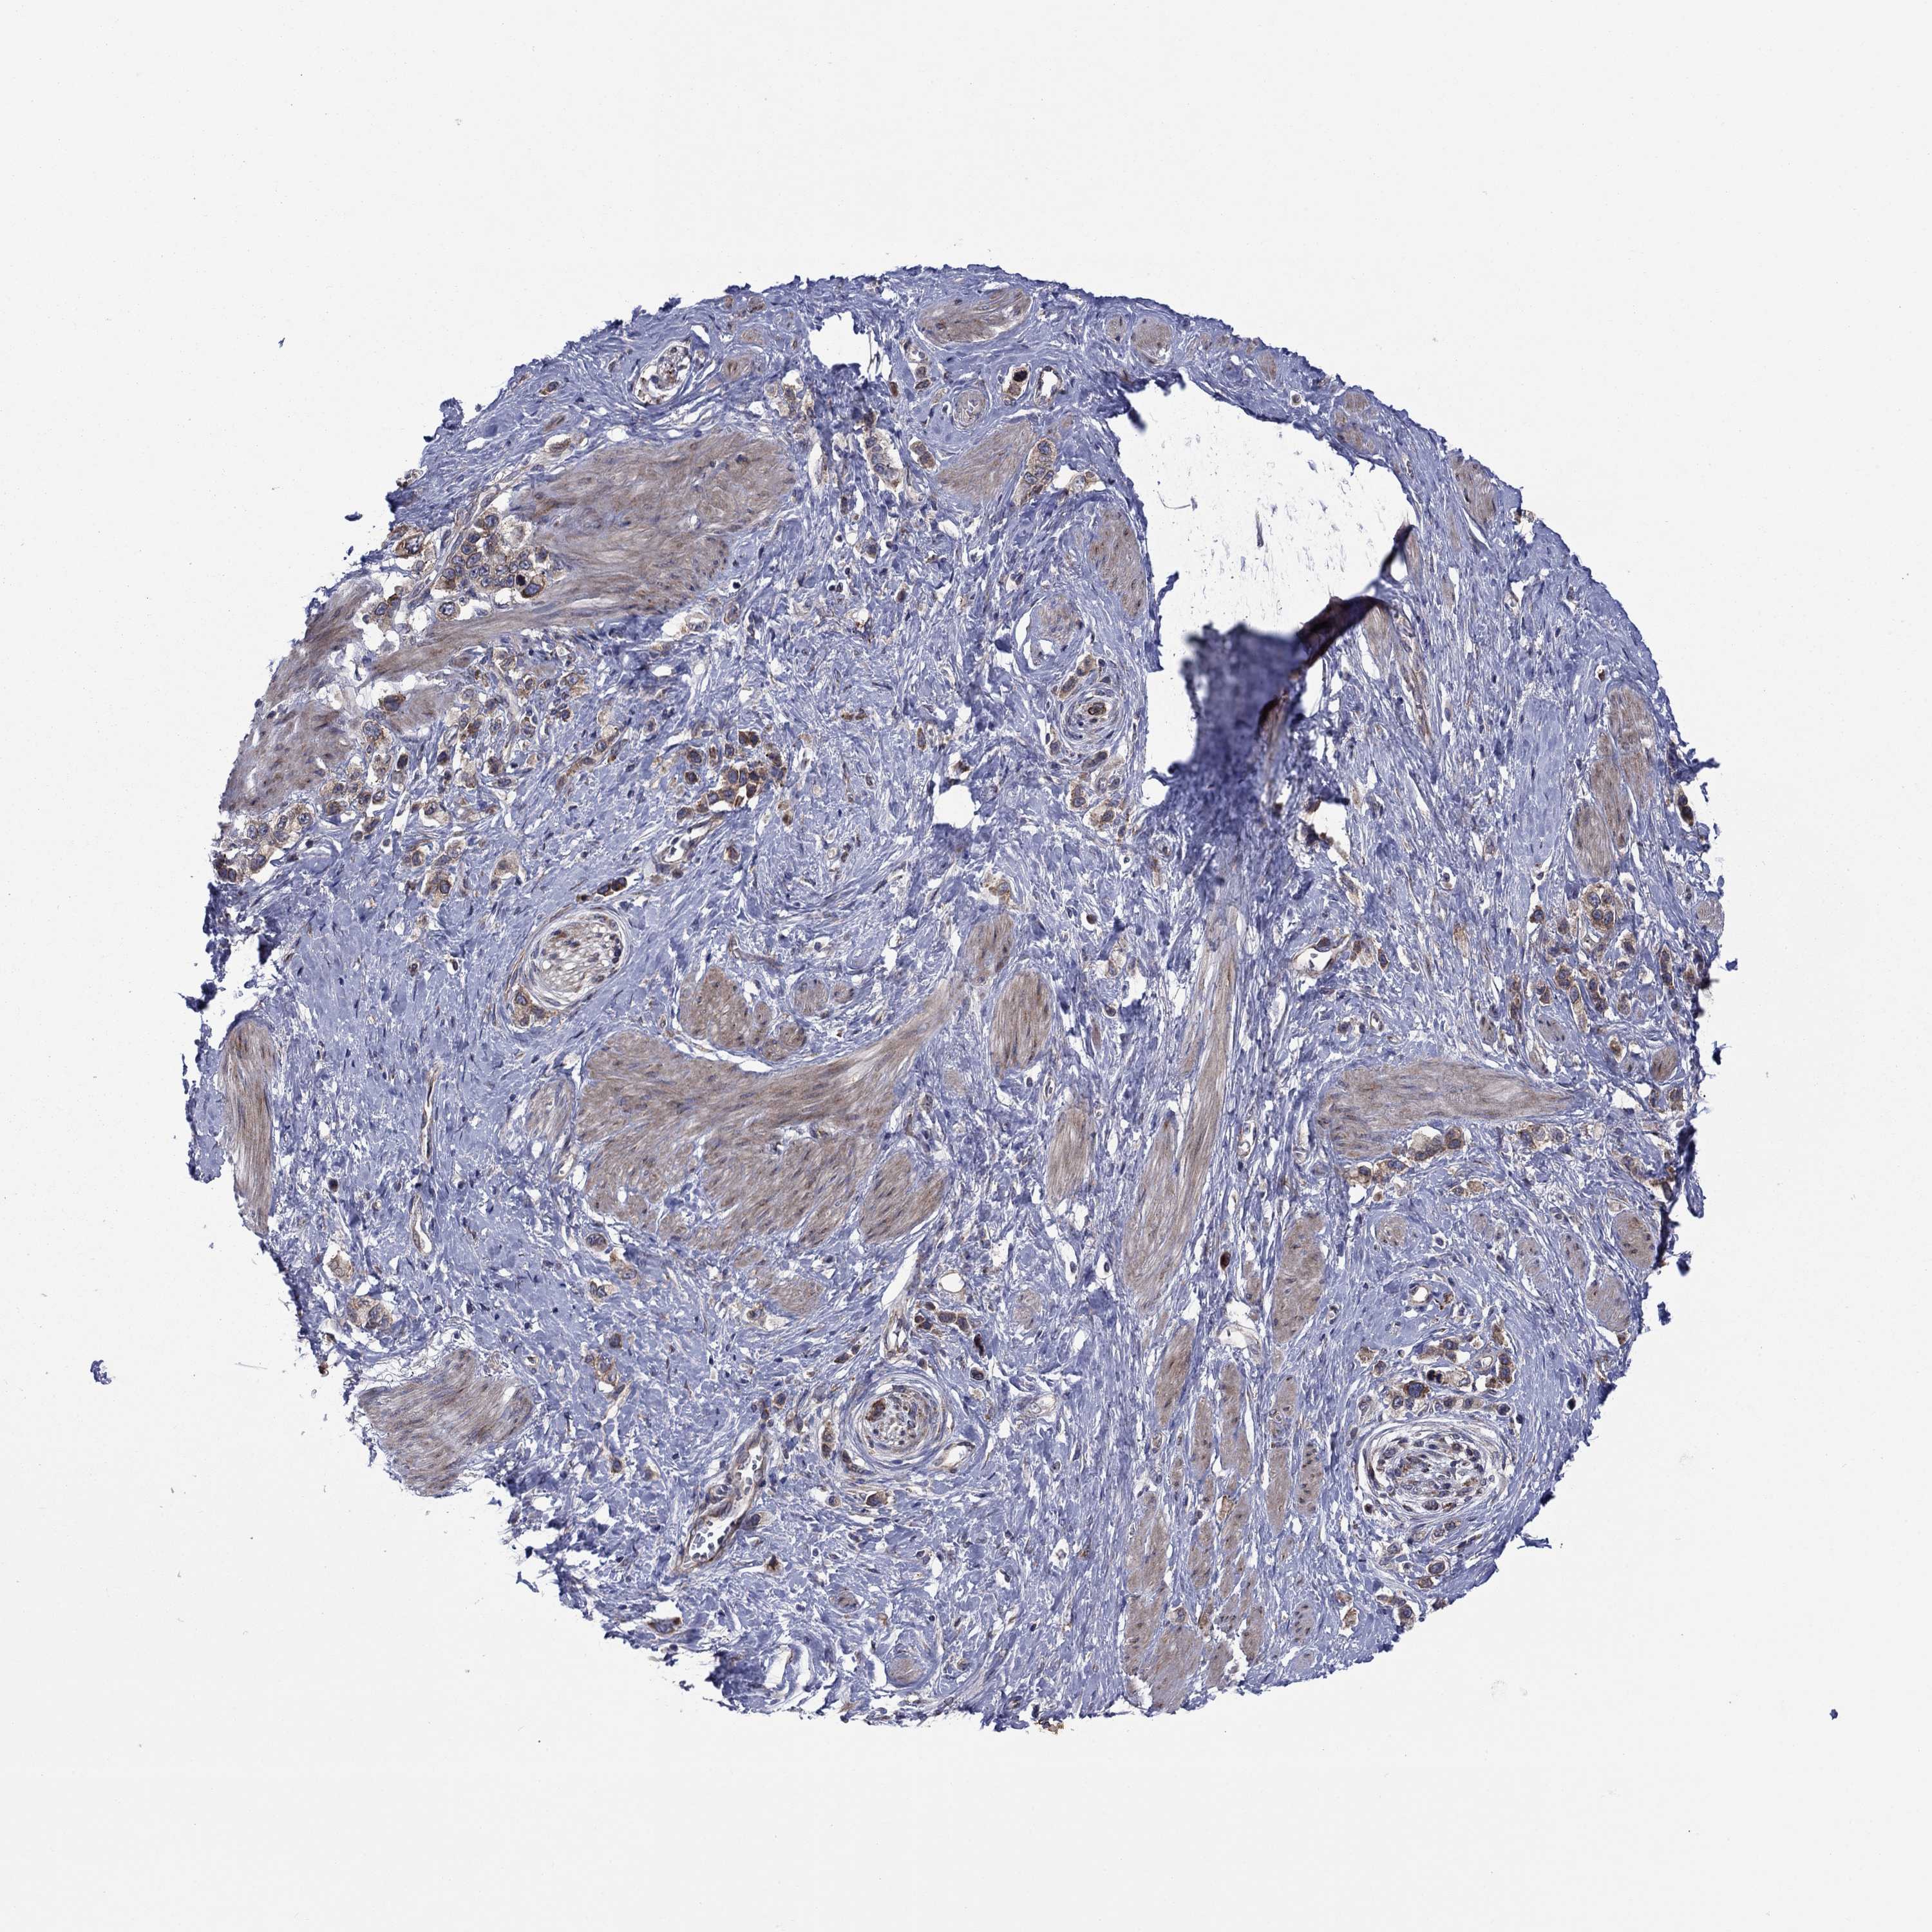

STOMACH CANCER - Protein expressioni

A mouse-over function shows sample information and annotation data. Click on an image to view it in a full screen mode. Samples can be filtered based on level of antibody staining by selecting one or several of the following categories: high, medium, low and not detected. The assay and annotation is described here.

Note that samples used for immunohistochemistry by the Human Protein Atlas do not correspond to samples in the TCGA dataset.

Antibody stainingi

Antibody staining in the annotated cell types in the current human tissue is reported as not detected, low, medium, or high, based on conventional immunohistochemistry profiling in selected tissues. This score is based on the combination of the staining intensity and fraction of stained cells.

Each image is clickable and will lead to virtual microscopy that enables deeper exploration of all samples and also displays staining intensity scores, fraction scores and subcellular localization as well as patient and tissue information for each sample.

Antibody HPA036159

Antibody HPA057384

Staining

High

Medium

Low

Not detected

Intensity

Strong

Moderate

Weak

Negative

Quantity

>75%

75%-25%

<25%

None

Location

Nuclear

Cytoplasmic/membranous

Cytoplasmic/membranous,nuclear

Adenocarcinoma, NOS

Adenocarcinoma, High grade